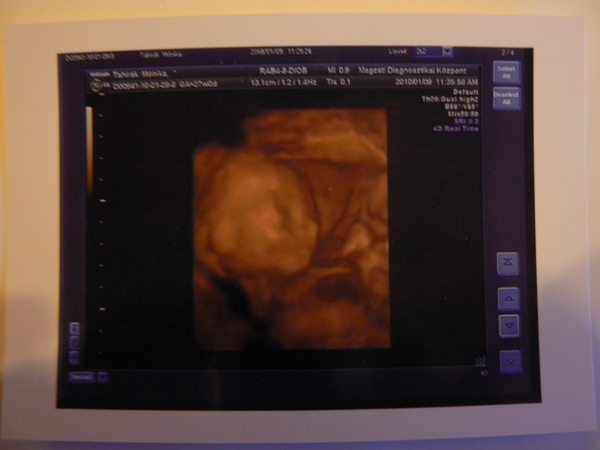

Magzatdiagnosztika Közp.

28. heti Uh Kép